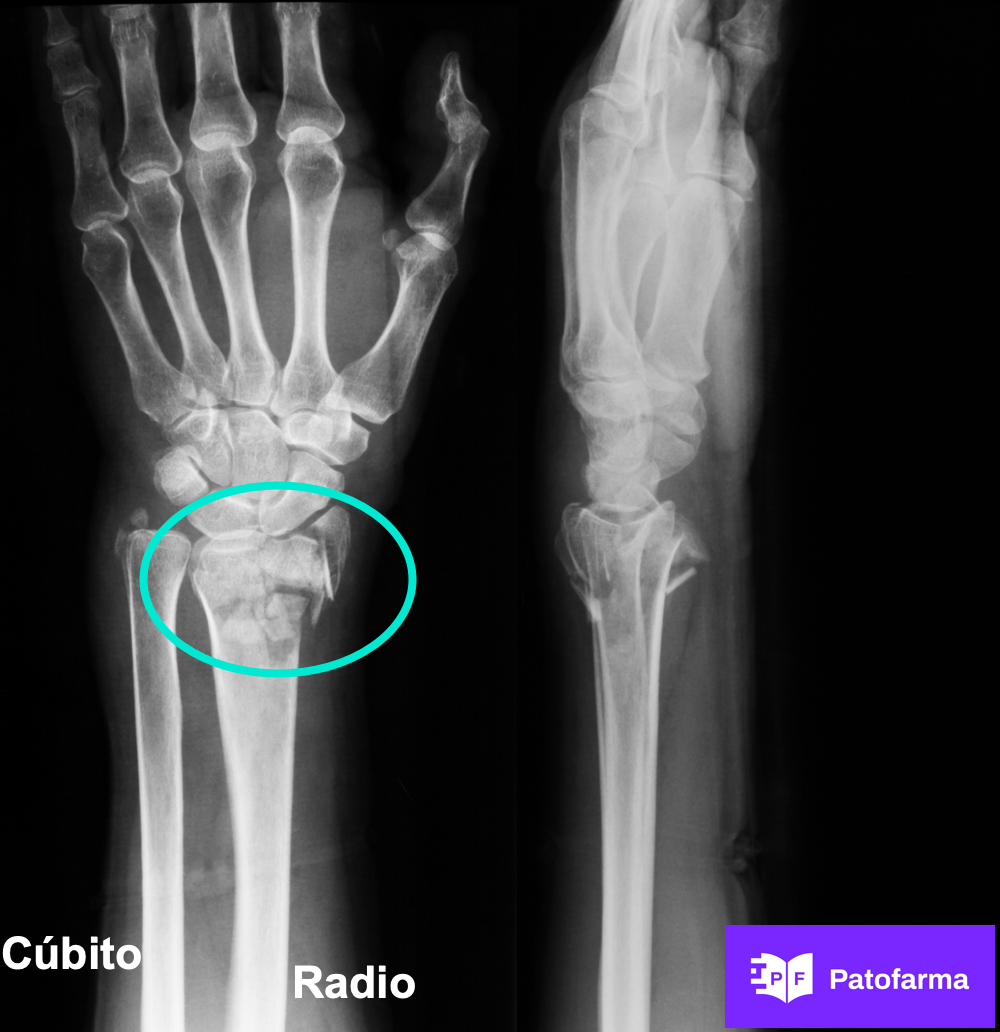

Vas a resolver el caso de una fractura del radio distal... que es el hueso del antebrazo que más se rompe al caerse de manos... y vas a aprender a describir dónde está la fractura en una radiografía real.

Distal es lejos del tronco. Y proximal es cerca del tronco.

Por eso... una fractura del radio distal es en la muñeca... y una fractura del radio proximal... en el codo".